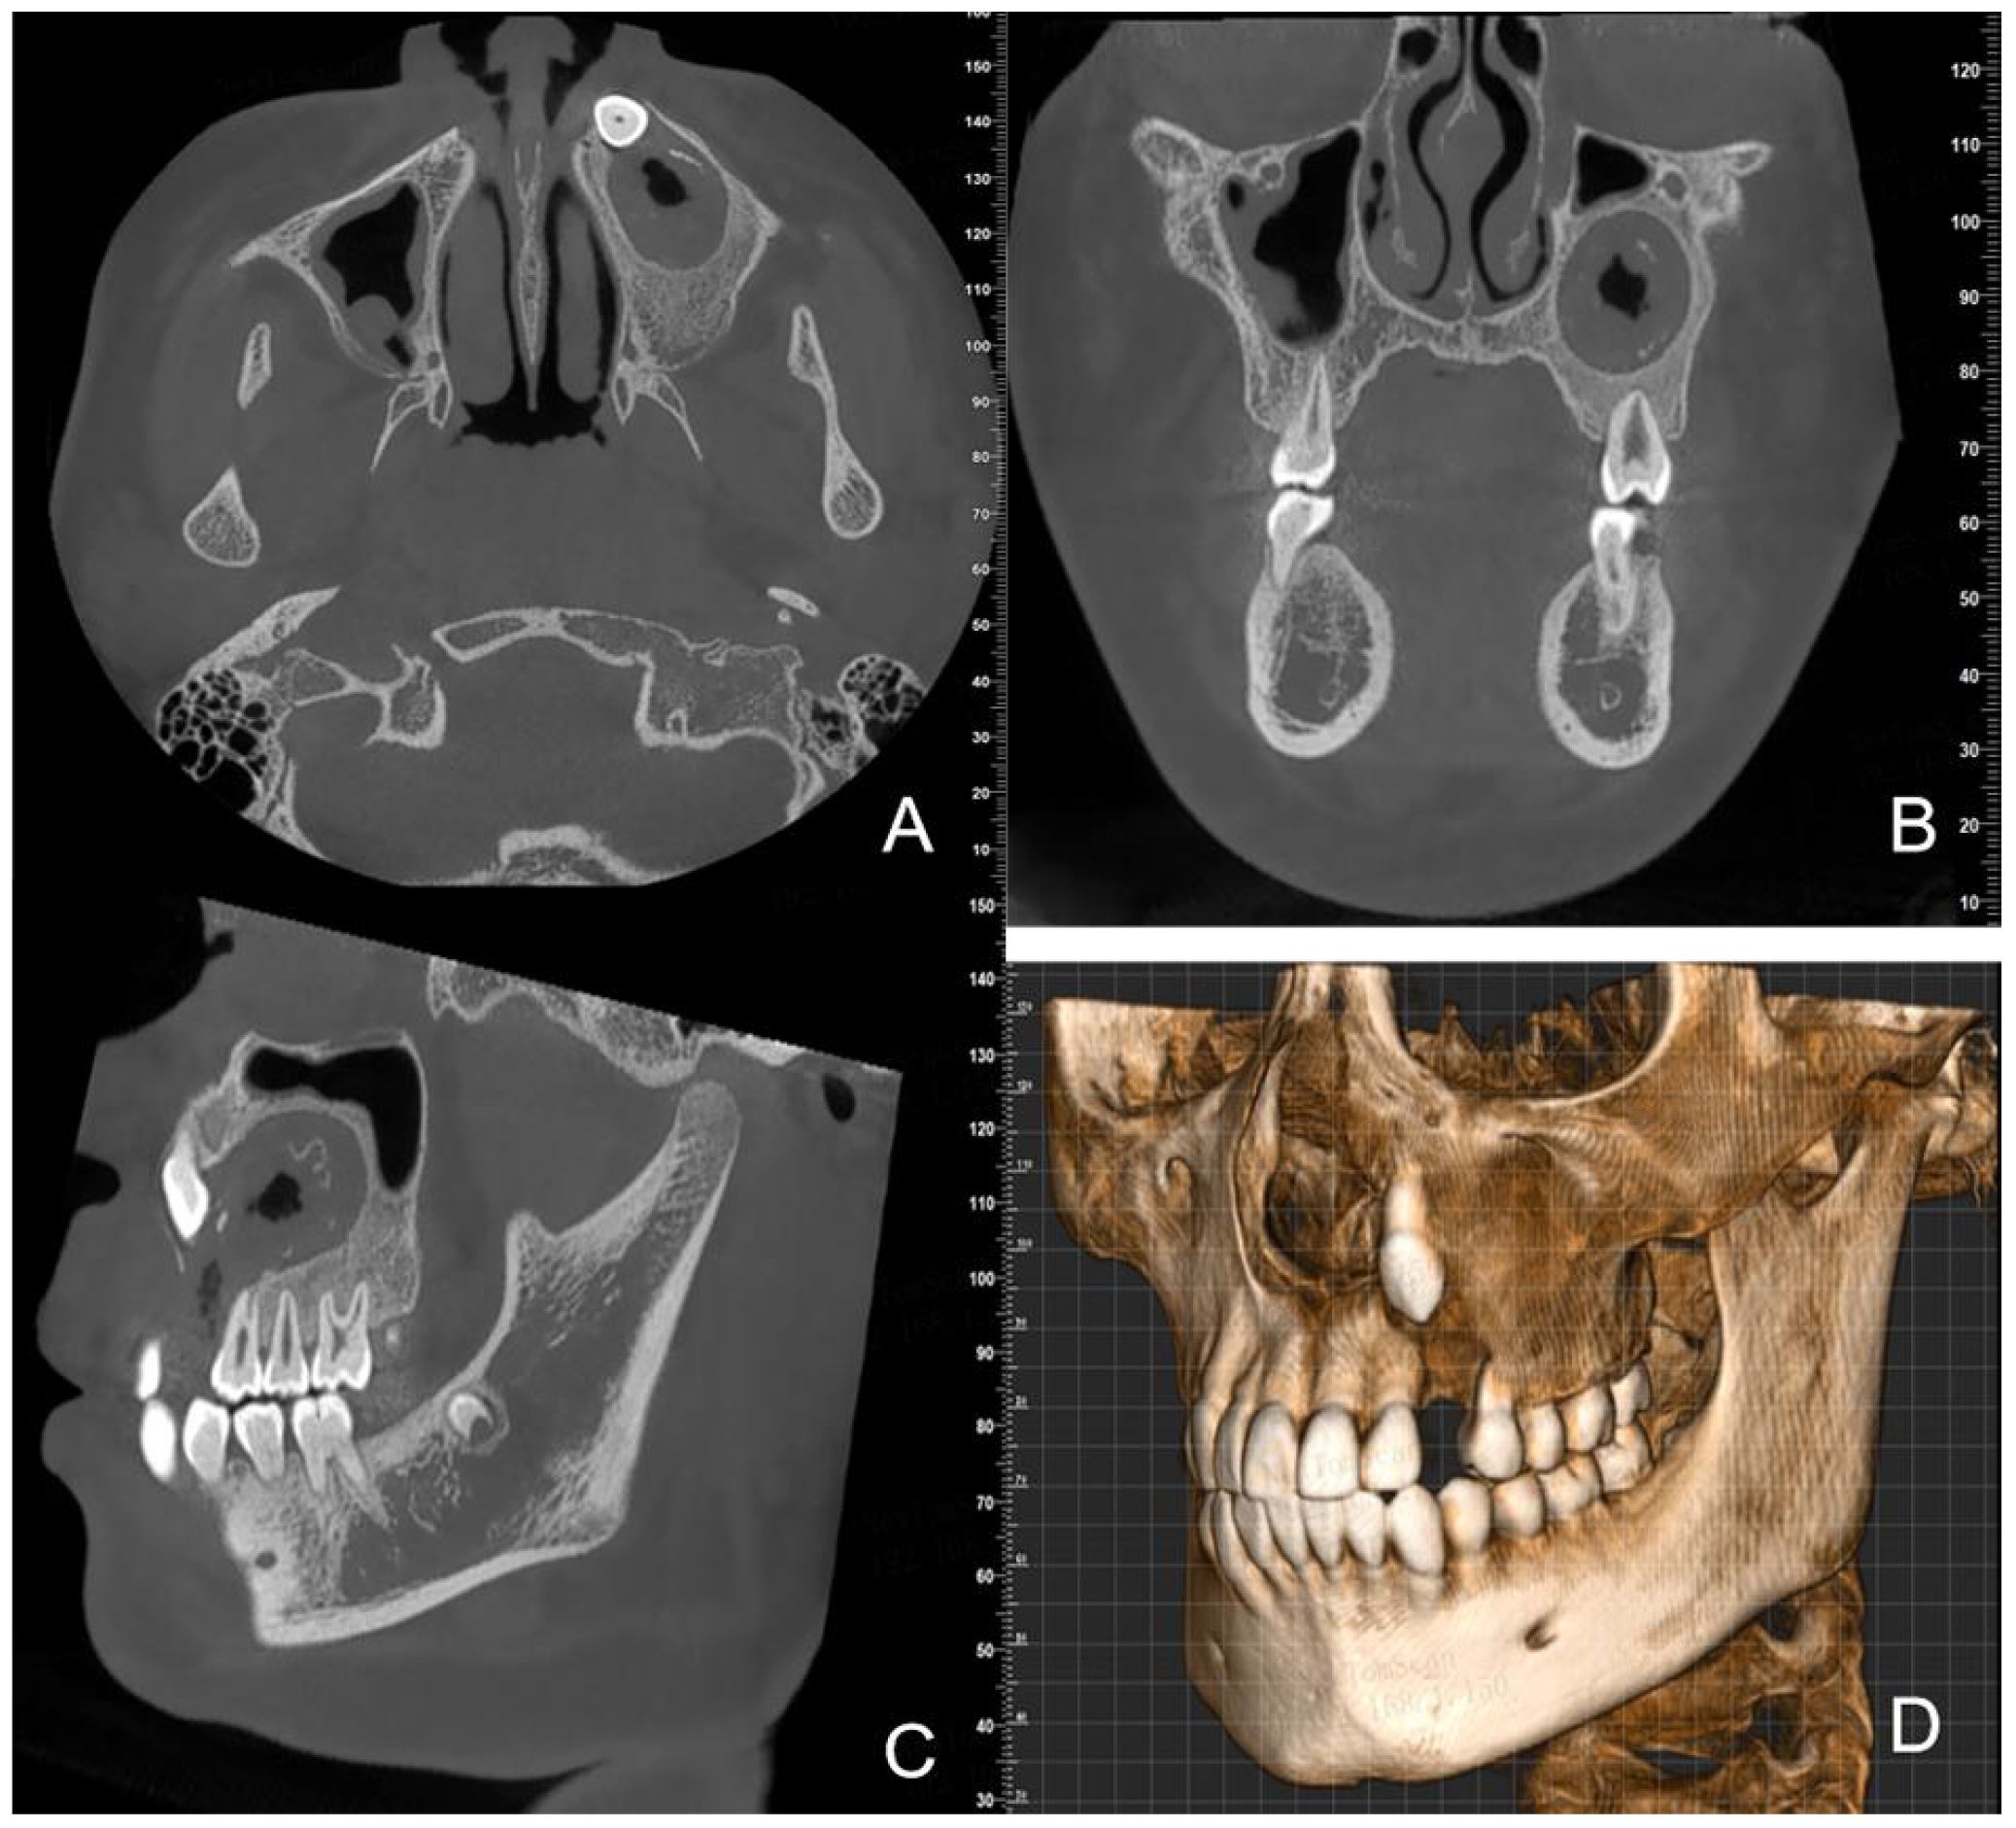

Dentinogenic ghost cell tumor (DGCT) is a rare odontogenic neoplasm that presents with nonspecific clinical manifestations and imaging features. It is more prevalent in elderly patients, with cases in children being extremely rare. This article presents a case study of a 10-year-old male patient who exhibited symptoms of swelling and pain in the left cheek for a duration of two weeks. Cone beam computed tomography (CBCT) demonstrated a hypodense lesion involving the left maxilla, with extension into the maxillary sinus and buccal cortical expansion. The patient underwent decompression, and histopathological examination of the intraoperative specimen suggested a diagnosis of calcifying odontogenic cyst (COC). One year after decompression, the patient underwent a tumor resection and the diagnosis of DGCT was confirmed by the post-operative pathology. Six months after tumor resection, CBCT showed complete bone remodelling in the lesion area. The patient is currently undergoing regular follow-up. This case provides an important reference for the diagnosis and treatment of pediatric DGCT, helping clinicians to develop individualised treatment plans.